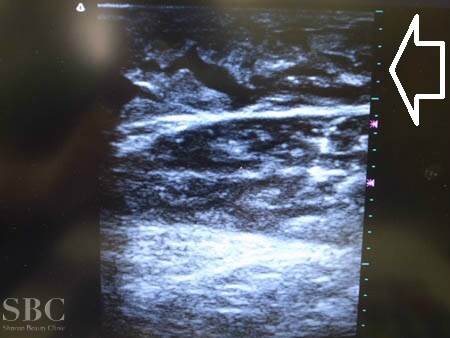

No.116809【脂肪吸引】湘南美容外科・脂肪吸引患者様数ダントツNo.1 あの有名な根こそぎ竹田先生の劇的ビフォーアフター!〜海外での脂肪吸引の再手術!左ふくらはぎ術中3Dタッチビューその1〜